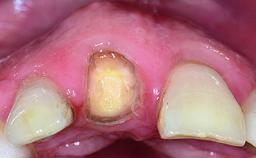

A 36-year-old male patient with a compromised maxillary central incisor was referred by his general dentist for consultation. The patient’s chief complaints were the gradual debonding of a temporary crown on the right central incisor and unsatisfactory esthetics due to an increasing diastema between the right central and lateral incisors. The patient reported a traumatic event some years previously, when a crown had been placed after root-canal treatment. The referring dentist wanted to provide a new crown restoration, but was concerned about the condition of the residual root. Anamnesis was negative for any other dental or periodontal pathology in the remaining dentition. The patient reported taking no medications: He was a smoker (10 to 15 cigs/day) and had realistic esthetic expectations.

Soft Tissue Anatomy Intact Defective

Bone Volume Horizontally and vertically sufficient Horizontally deficient Deficient vertically or deficient vertically AND horizontally